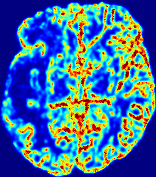

4.3.1 Advection Imaging via Advection-Diffusion

Slice #1Slice #2Slice #3Slice #4Slice #5Slice #6𝐕gt𝟐subscriptnormsuperscript𝐕gt2\|\bf{V}^{\text{gt}}\|_{2}Refer to captionRefer to captionRefer to captionRefer to captionRefer to captionRefer to caption𝐕est𝟐subscriptnormsuperscript𝐕est2\|\bf{V}^{\text{est}}\|_{2}Refer to captionRefer to captionRefer to captionRefer to captionRefer to captionRefer to captionRefer to caption1.51.51.51.21.21.20.90.90.90.60.60.60.30.30.30.00.00.0(mm/s)𝑚𝑚𝑠(mm/s)Destsuperscript𝐷estD^{\text{est}}Refer to captionRefer to captionRefer to captionRefer to captionRefer to captionRefer to captionRefer to caption0.0150.0150.0150.0120.0120.0120.0090.0090.0090.0060.0060.0060.0030.0030.0030.0000.0000.000(mm2/s)𝑚superscript𝑚2𝑠(mm^{2}/s)

Figure 14: PIANO identifiability testing: advection imaging via advection-diffusion. Top row shows 𝐕gt2subscriptnormsuperscript𝐕gt2\|{\bf{V}}^{\text{gt}}\|_{2} used for simulating ground truth pure advection. Rows below show the estimated 𝐕est2subscriptnormsuperscript𝐕est2\|{\bf{V}}^{\text{est}}\|_{2} and Destsuperscript𝐷estD^{\text{est}} on corresponding slices. Note that the plotted value scale for Destsuperscript𝐷estD^{\text{est}} is 0.01 of that for 𝐕gt2subscriptnormsuperscript𝐕gt2\|{\bf{V}}^{\text{gt}}\|_{2} and 𝐕est2subscriptnormsuperscript𝐕est2\|{\bf{V}}^{\text{est}}\|_{2}.

We use the same ‘Advection Imaging’ simulation of Sec. 4.2.1 as the concentration dataset for PIANO. However, instead of modeling pure advection (Eq. 15), we let PIANO estimate both velocity 𝐕estsuperscript𝐕est{\bf{V}}^{\text{est}} and diffusivity Destsuperscript𝐷estD^{\text{est}} via the advection-diffusion PDE (Eq. 2) underlying the proposed PIANO model. Fig. 14 shows the estimated 𝐕est2,subscriptnormsuperscript𝐕est2\|{\bf{V}}^{\text{est}}\|_{2}, and Destsuperscript𝐷estD^{\text{est}} fields for one patient. Although PIANO has the freedom to estimate both a velocity and a diffusivity field from pure advection, PIANO differentiates well between advection and diffusion: the estimated 𝐕est2subscriptnormsuperscript𝐕est2\|{\bf{V}}^{\text{est}}\|_{2} successfully reproduces the ground truth 𝐕gt2subscriptnormsuperscript𝐕gt2\|{\bf{V}}^{\text{gt}}\|_{2} governing the simulated advection process, just as it already did in the ‘Advection Imaging via Advection’ test (Fig. 12). More importantly, the estimated diffusivity Destsuperscript𝐷estD^{\text{est}} is orders of magnitudes smaller than 𝐕est2subscriptnormsuperscript𝐕est2\|{\bf{V}}^{\text{est}}\|_{2}, indicating the estimated diffusion is negligible compared to the estimated advection, which is highly consistent with the underlying pure advection of the simulated data.